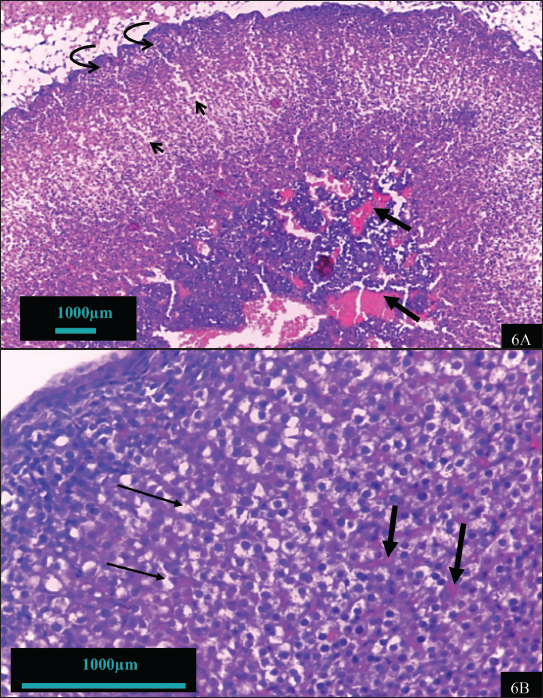

Hypothyroidism causes obvious structural changes in the adrenal gland (Fig. 6a and 6b). The cortex appeared more rigid than the normal cortex (Fig. 5a). There was obvious disorganization of the zona fasciculate cells, with the cords seeming to overlap with each other. The cells were smaller and more irregular in shape and size with some pyknotic nucleus observed compared to the control. The cytoplasm was also much less with fewer fatty vacuoles seen, e.g., the group in Figure 6a is compared with the control group in Figure 5a. In the medulla region, cellular hyperplasia was observed, causing the area to become thickened, and dilatation and congestion of blood vessels showed areas of hemorrhages.

Fig. 6. Histosmorphological of adrenal gland tissue in hypothyroidism group showing degenerated cells near the capsule (curved arrow) with vacuolation (arrowhead) and vascular hypertrophy (thick arrow) of AM (6A) (100 X). Congestion of sinusoids (thick arrow) and necrosis cells (thin arrow) (6B) (400 X).